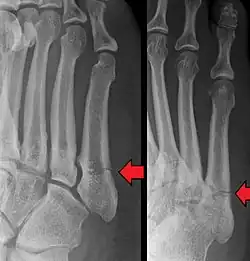

- Proximal diaphysis, typically stress fracture.[12][13]

- Metaphysis: Jones fracture[14]

-Tuberosity: Pseudo-Jones fracture[15] (avulsion fracture).[15]

Normal anatomy:

- Apophysis: Normal at 10 - 16 years.[16]

- Os vesalianum, an accessory bone.[17]

Other proximal fifth metatarsal fractures exist, although they are not as problematic as a Jones fracture. If the fracture enters the intermetatarsal joint, it is a Jones fracture. If, however, it enters the tarsometatarsal joint, then it is likely an avulsion fracture caused by pull from the fibularis brevis tendon. An avulsion fracture at the base of the fifth metatarsal is sometimes called a "dancer's fracture" or a "pseudo Jones fracture", and usually responds readily to non-operative treatment.[18] The X-ray appearance of the developmental "apophysis" in this area may have some resemblance of a fracture, but is not a fracture; it is the secondary ossification center of the metatarsal bone. It is a normal finding that occurs at this site in adolescents.[19] If an injury to that area has occurred, the physician is often able to interpret certain radiographic clues to make the differentiation. An avulsion fracture at this location is typically extra-articular and oriented transversally as compared to the longitudinal orientation of an unfused apophysis.[19]